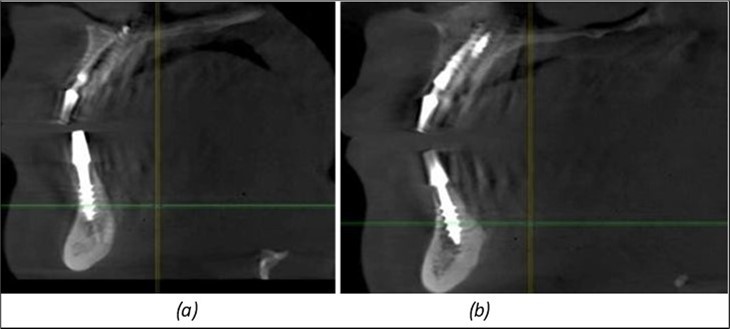

Figure 13.Corticobasal BCS implants fixed between the vestibular and lingual cortices with support on the basal bone: (a) BCS fixed between the lateral cortices; (b) BCS implant with support on the basal cortex.